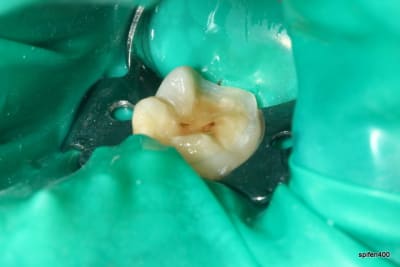

31/10/2011 à 18h09

tiens je me suis chronométré :)

28min :) lol

bon celui la etait un peu long, car provisoire collé au cvi cause durée avec le provisoire trop longue....

donc dur a déposer et obligé d'enlever les résidu de cvi aux US...

ceux qui font pas d'onlay vous proposez quoi là ?

patiente de 13 ans ...

heu spifen 400 c'est pas de la pub lol

Ca ressemble à un beau MIH avec un confrère qui a fait des trucs bizarres avec un amalgame.

Oui MIH déjà avec une belle récidive de carie. Je pense que dans un cas comme ça le compo est voué très vite à l’Échec...